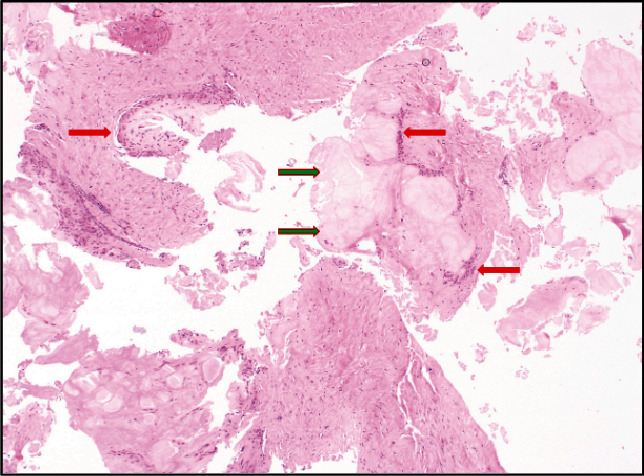

跟腱修复术后数年,之前的手术部位周围形成痛风性结石是一种极为罕见的病症,文献中仅记载过三例。在本病例中,我们报告了一名 53 岁男性的病例,他在两年半前进行过跟腱修复手术,并且没有痛风的临床病史,但在对跟腱进行必要的翻修手术时,我们发现他在初次手术修复时使用的不可吸收缝线周围出现了痛风性结石。这个病例和之前的三个病例都涉及到不可吸收缝合线的使用,这些缝合线有可能成为手术多年后痛风性跟腱炎形成的巢穴,即使是没有痛风临床病史的患者也可能出现痛风性跟腱炎。临床医生必须注意这种罕见的临床表现,因为潜在的后遗症包括感染过程和需要进行翻修手术。

The formation of gouty tophi surrounding the prior surgical site years after an Achilles tendon repair is an extremely rare presentation for which only three previous cases have been documented in the literature. In this case, we report the presentation of a 53-year-old male who had an Achilles tendon repair two and a half years prior and no clinical history of gout, yet during the necessary revision procedure of his Achilles tendon, he was found to have gouty tophi surrounding the nonabsorbable sutures used during his initial surgical repair. This case presentation and the three prior ones all involve the use of nonabsorbable sutures, and these sutures may potentially serve as a nidus for the formation of gouty tophi years after a surgical procedure, even in patients who do not have a clinical history of gout. It is important for clinicians to be aware of this rare clinical presentation as potential sequelae include infectious processes and the need for revision procedures.